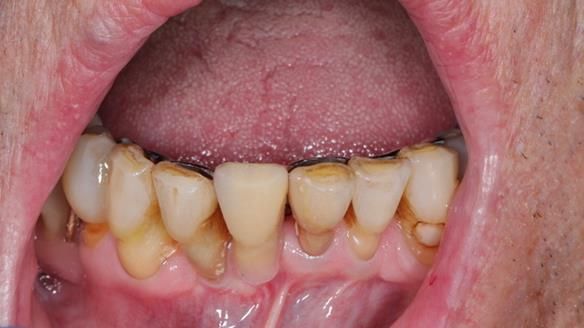

Welcome to my Newsletter 54 showing the making and fitting of dentures (a complete upper metal reinforced denture, a lower immediate partial denture and a definitive Scandinavian designed, metal based lower partial denture) for David, a 75 -year-old man. The full protocol workflow is presented including the use of dentate photographs to mimic his natural teeth.

- The remaining lower 9 teeth had periodontal disease. Syed Abad, Specialist in Periodontics at the practice managed it.

- The soft tissues of the mouth appeared healthy.